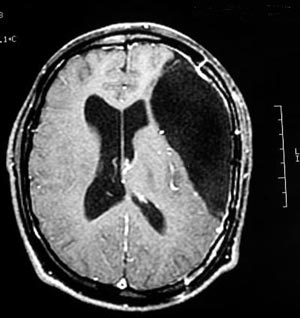

2d) Gliose (processo cicatricial do cérebro)

Figura 52 - Ressonância nuclear magnética pré-operatória.

Figura 54 - Ressonância nuclear magnética pós-operatória mostrando extensa ressecção frontal. Quando o paciente apresenta lesão extensa como esse caso, muitas vezes somente uma ressecção igualmente extensa deixará o paciente livre de crises.